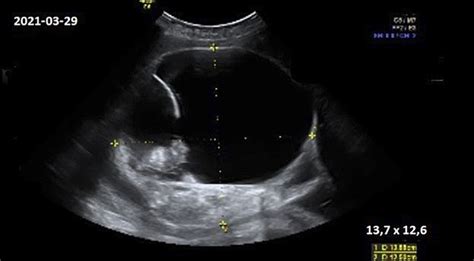

1. Ultragarsinis tyrimas (echoskopija):

Tai pats populiariausias ir neinvazinis metodas. Pirmieji lyties požymiai gali būti pastebėti jau nuo 11-os nėštumo savaitės, tačiau tiksliausias nustatymas paprastai atliekamas antrojo trimestro metu (apie 18-22 savaitę), kai vaisius yra didesnis ir jo lytiniai organai aiškiau matomi. Metodo efektyvumas vėlesniu nėštumo laikotarpiu siekia nuo 93 iki 100%. Tačiau svarbu atsiminti, kad ultragarsas gali būti iškreiptas dėl vaisiaus padėties, lyties vystymosi anomalijų ar kitų veiksnių.